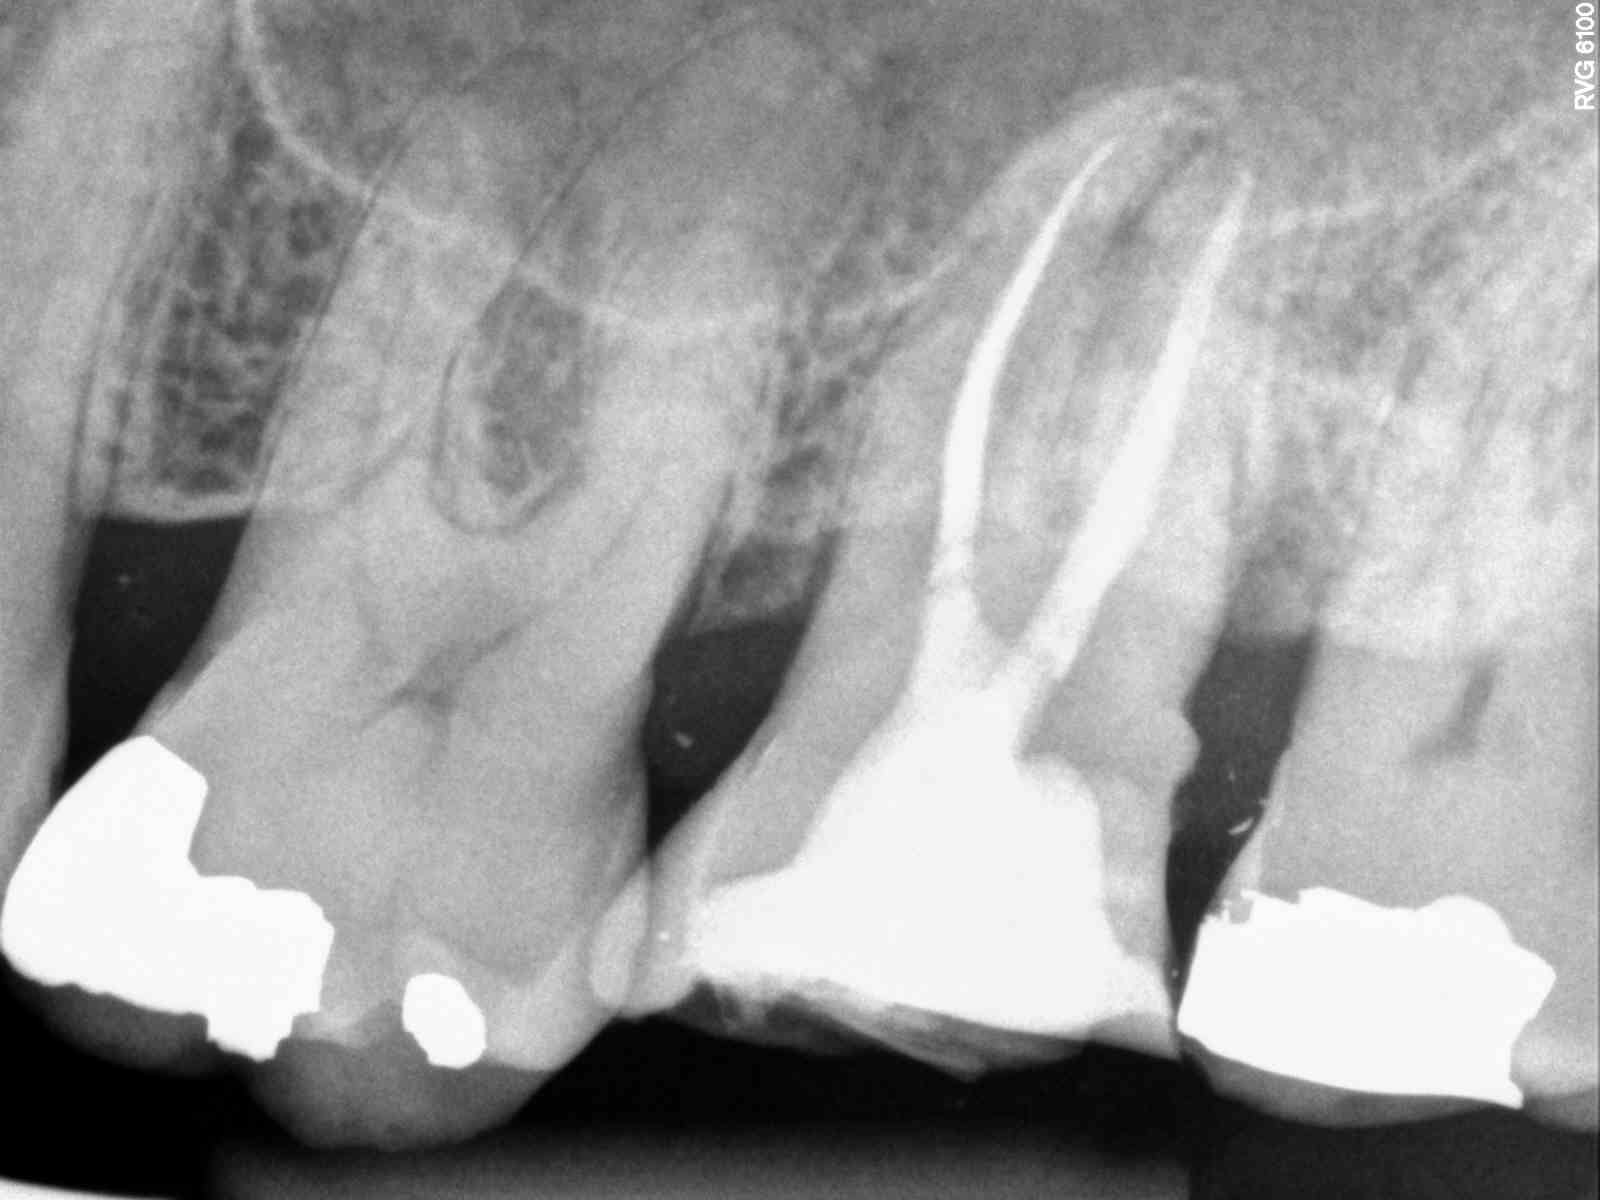

MB1 and MB2 joined about 3mm from apex and were >.5mm apart. MB3 was >.5mm from MB2

All 3 MB canals had distinct portal of entry. Mb1 and Mb2 had significant anastomosis with each other

| Can kind or see the three orifices |

| Can not really see all three |